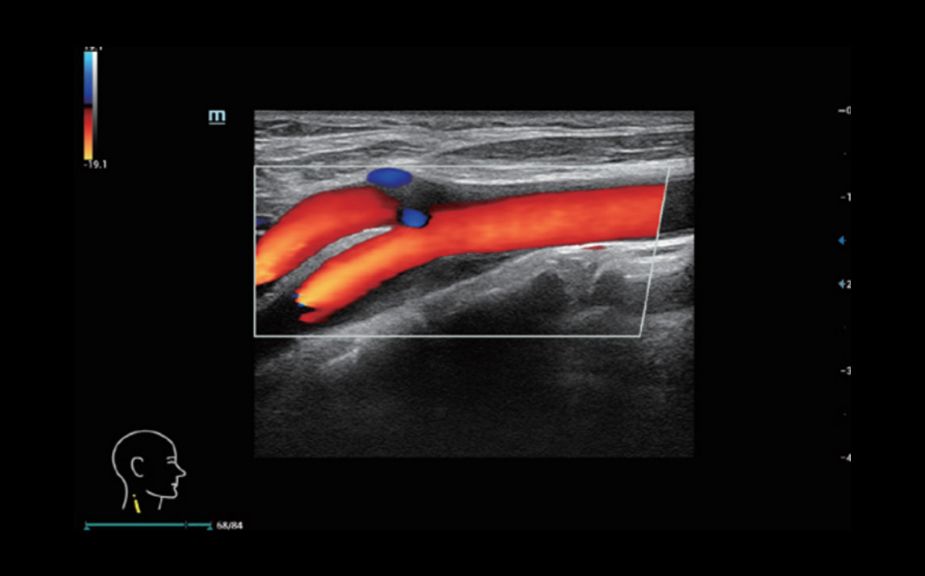

–Ě–ĺ–≤–Ķ–Ļ—ą–ł–Ļ –Ņ–ĺ–ī—Ö–ĺ–ī –ļ –ł–∑—É—á–Ķ–Ĺ–ł—é —Ā–ĺ—Ā—É–ī–ł—Ā—ā–ĺ–Ļ –≥–Ķ–ľ–ĺ–ī–ł–Ĺ–į–ľ–ł–ļ–ł: V Flow

–ė—Ā–Ņ–ĺ–Ľ—Ć–∑—É—é—ā—Ā—Ź –ľ–į—Ä–ļ–ł—Ä–ĺ–≤–į–Ĺ–Ĺ—č–Ķ —Ü–≤–Ķ—ā–ĺ–ľ –≤–Ķ–ļ—ā–ĺ—Ä–į –ī–Ľ—Ź –ł–Ĺ–ī–ł–ļ–į—Ü–ł–ł –∑–Ĺ–į—á–Ķ–Ĺ–ł—Ź —Ā–ļ–ĺ—Ä–ĺ—Ā—ā–ł –ł –Ĺ–į–Ņ—Ä–į–≤–Ľ–Ķ–Ĺ–ł—Ź –ī–≤–ł–∂–Ķ–Ĺ–ł—Ź –ļ–Ľ–Ķ—ā–ĺ–ļ –ļ—Ä–ĺ–≤–ł. –Ď–Ľ–į–≥–ĺ–ī–į—Ä—Ź —Ā–≤–Ķ—Ä—Ö–≤—č—Ā–ĺ–ļ–ĺ–Ļ —á–į—Ā—ā–ĺ—ā–Ķ –ļ–į–ī—Ä–ĺ–≤ V Flow –ĺ–Ī–Ķ—Ā–Ņ–Ķ—á–ł–≤–į–Ķ—ā —á—Ä–Ķ–∑–≤—č—á–į–Ļ–Ĺ–ĺ —á–Ķ—ā–ļ—É—é, —ā–ĺ—á–Ĺ—É—é –ł –Ĺ–Ķ–∑–į–≤–ł—Ā–ł–ľ—É—é –ĺ—ā —É–≥–Ľ–į –ļ–ĺ–ľ–Ņ–Ľ–Ķ–ļ—Ā–Ĺ—É—é –ĺ—Ü–Ķ–Ĺ–ļ—É —Ā–ĺ—Ā—É–ī–ł—Ā—ā–ĺ–Ļ –≥–Ķ–ľ–ĺ–ī–ł–Ĺ–į–ľ–ł–ļ–ł —Ā –≤–ĺ–∑–ľ–ĺ–∂–Ĺ–ĺ—Ā—ā—Ć—é –≤—Ā–Ķ—Ā—ā–ĺ—Ä–ĺ–Ĺ–Ĺ–Ķ–≥–ĺ –į–Ĺ–į–Ľ–ł–∑–į.

V Flow

–Ě–ĺ–≤–Ķ–Ļ—ą–ł–Ļ –Ņ–ĺ–ī—Ö–ĺ–ī –ļ –ł–∑—É—á–Ķ–Ĺ–ł—é —Ā–ĺ—Ā—É–ī–ł—Ā—ā–ĺ–Ļ –≥–Ķ–ľ–ĺ–ī–ł–Ĺ–į–ľ–ł–ļ–ł: V Flow

–ė—Ā–Ņ–ĺ–Ľ—Ć–∑—É—é—ā—Ā—Ź –ľ–į—Ä–ļ–ł—Ä–ĺ–≤–į–Ĺ–Ĺ—č–Ķ —Ü–≤–Ķ—ā–ĺ–ľ –≤–Ķ–ļ—ā–ĺ—Ä–į –ī–Ľ—Ź –ł–Ĺ–ī–ł–ļ–į—Ü–ł–ł –∑–Ĺ–į—á–Ķ–Ĺ–ł—Ź —Ā–ļ–ĺ—Ä–ĺ—Ā—ā–ł –ł –Ĺ–į–Ņ—Ä–į–≤–Ľ–Ķ–Ĺ–ł—Ź –ī–≤–ł–∂–Ķ–Ĺ–ł—Ź –ļ–Ľ–Ķ—ā–ĺ–ļ –ļ—Ä–ĺ–≤–ł. –Ď–Ľ–į–≥–ĺ–ī–į—Ä—Ź —Ā–≤–Ķ—Ä—Ö–≤—č—Ā–ĺ–ļ–ĺ–Ļ —á–į—Ā—ā–ĺ—ā–Ķ –ļ–į–ī—Ä–ĺ–≤ V Flow –ĺ–Ī–Ķ—Ā–Ņ–Ķ—á–ł–≤–į–Ķ—ā —á—Ä–Ķ–∑–≤—č—á–į–Ļ–Ĺ–ĺ —á–Ķ—ā–ļ—É—é, —ā–ĺ—á–Ĺ—É—é –ł –Ĺ–Ķ–∑–į–≤–ł—Ā–ł–ľ—É—é –ĺ—ā —É–≥–Ľ–į –ļ–ĺ–ľ–Ņ–Ľ–Ķ–ļ—Ā–Ĺ—É—é –ĺ—Ü–Ķ–Ĺ–ļ—É —Ā–ĺ—Ā—É–ī–ł—Ā—ā–ĺ–Ļ –≥–Ķ–ľ–ĺ–ī–ł–Ĺ–į–ľ–ł–ļ–ł —Ā –≤–ĺ–∑–ľ–ĺ–∂–Ĺ–ĺ—Ā—ā—Ć—é –≤—Ā–Ķ—Ā—ā–ĺ—Ä–ĺ–Ĺ–Ĺ–Ķ–≥–ĺ –į–Ĺ–į–Ľ–ł–∑–į.

V Flow